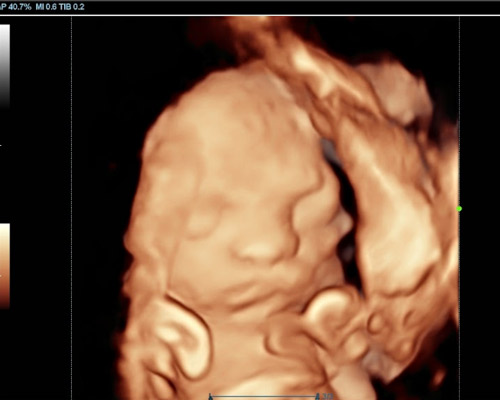

- See your baby’s face clearly using HD Live imaging

- Watch natural movements and expressions

Our 3D/4D Bonding Scan is a truly special experience, allowing you to connect with your baby like never before. Using advanced HD Live technology, you can enjoy clear images and even catch glimpses of facial expressions.

Our Scans